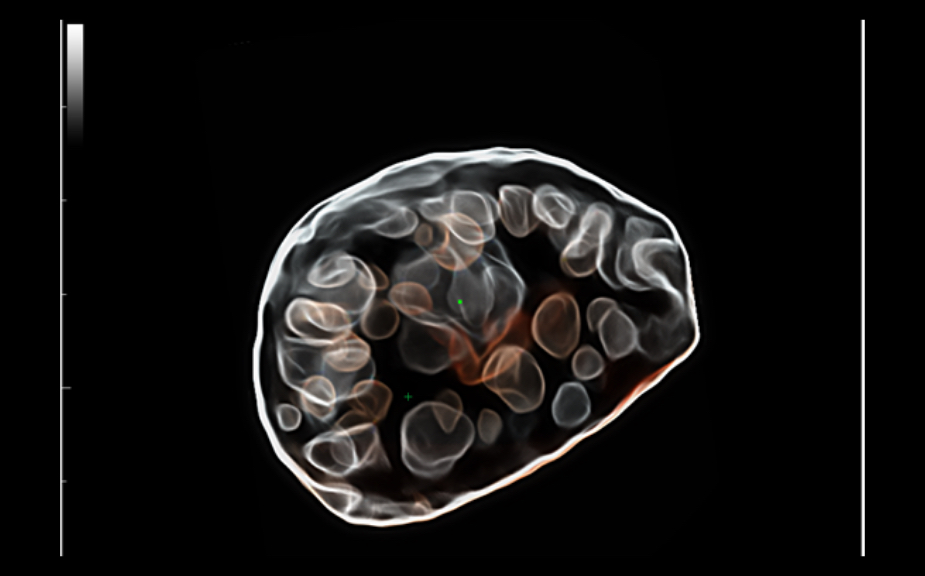

DC-80A con X-Insight mette a disposizione strumenti di una intelligenza eccezionale specifici per la cura della donna, dalla fertilit├Ā allo screening prenatale, e al post partum.

Immagini cliniche